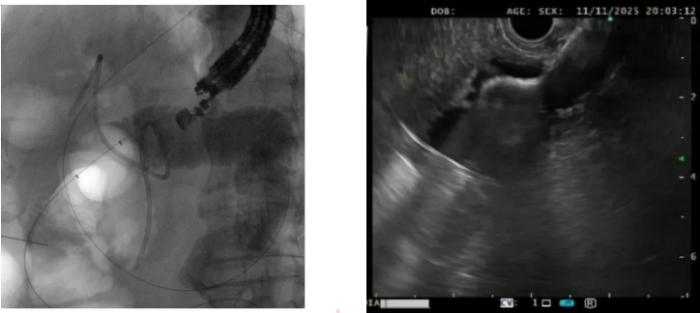

EUS-GE 对医生的操作精准度、临床经验和应急处理能力要求极高。目前国内EUS-GE 临床应用尚未普及,仅部分发达地区大型医院具备开展该技术的条件。该手术操作过程中需实时通过超声定位,避开血管、肝脏等重要脏器,同时确保吻合口牢固、通畅,避免出血、穿孔等并发症的发生。为此,消化内科内镜医生、麻醉医生及护理团队提前制定了详细的手术预案,11日下午为张大爷施行了手术。术中医护团队密切配合、精准操作,应用胃镜将超滑导丝送入狭窄远端肠管,在X线定位下送入球囊封堵远端空肠,注入造影剂使空肠近端显影,使用超声内镜在胃腔内定位,将双蘑菇头支架精准置入空肠与胃之间,仅用 40 分钟就顺利完成通道建立,全程无出血、无并发症发生。

X线下见支架在位